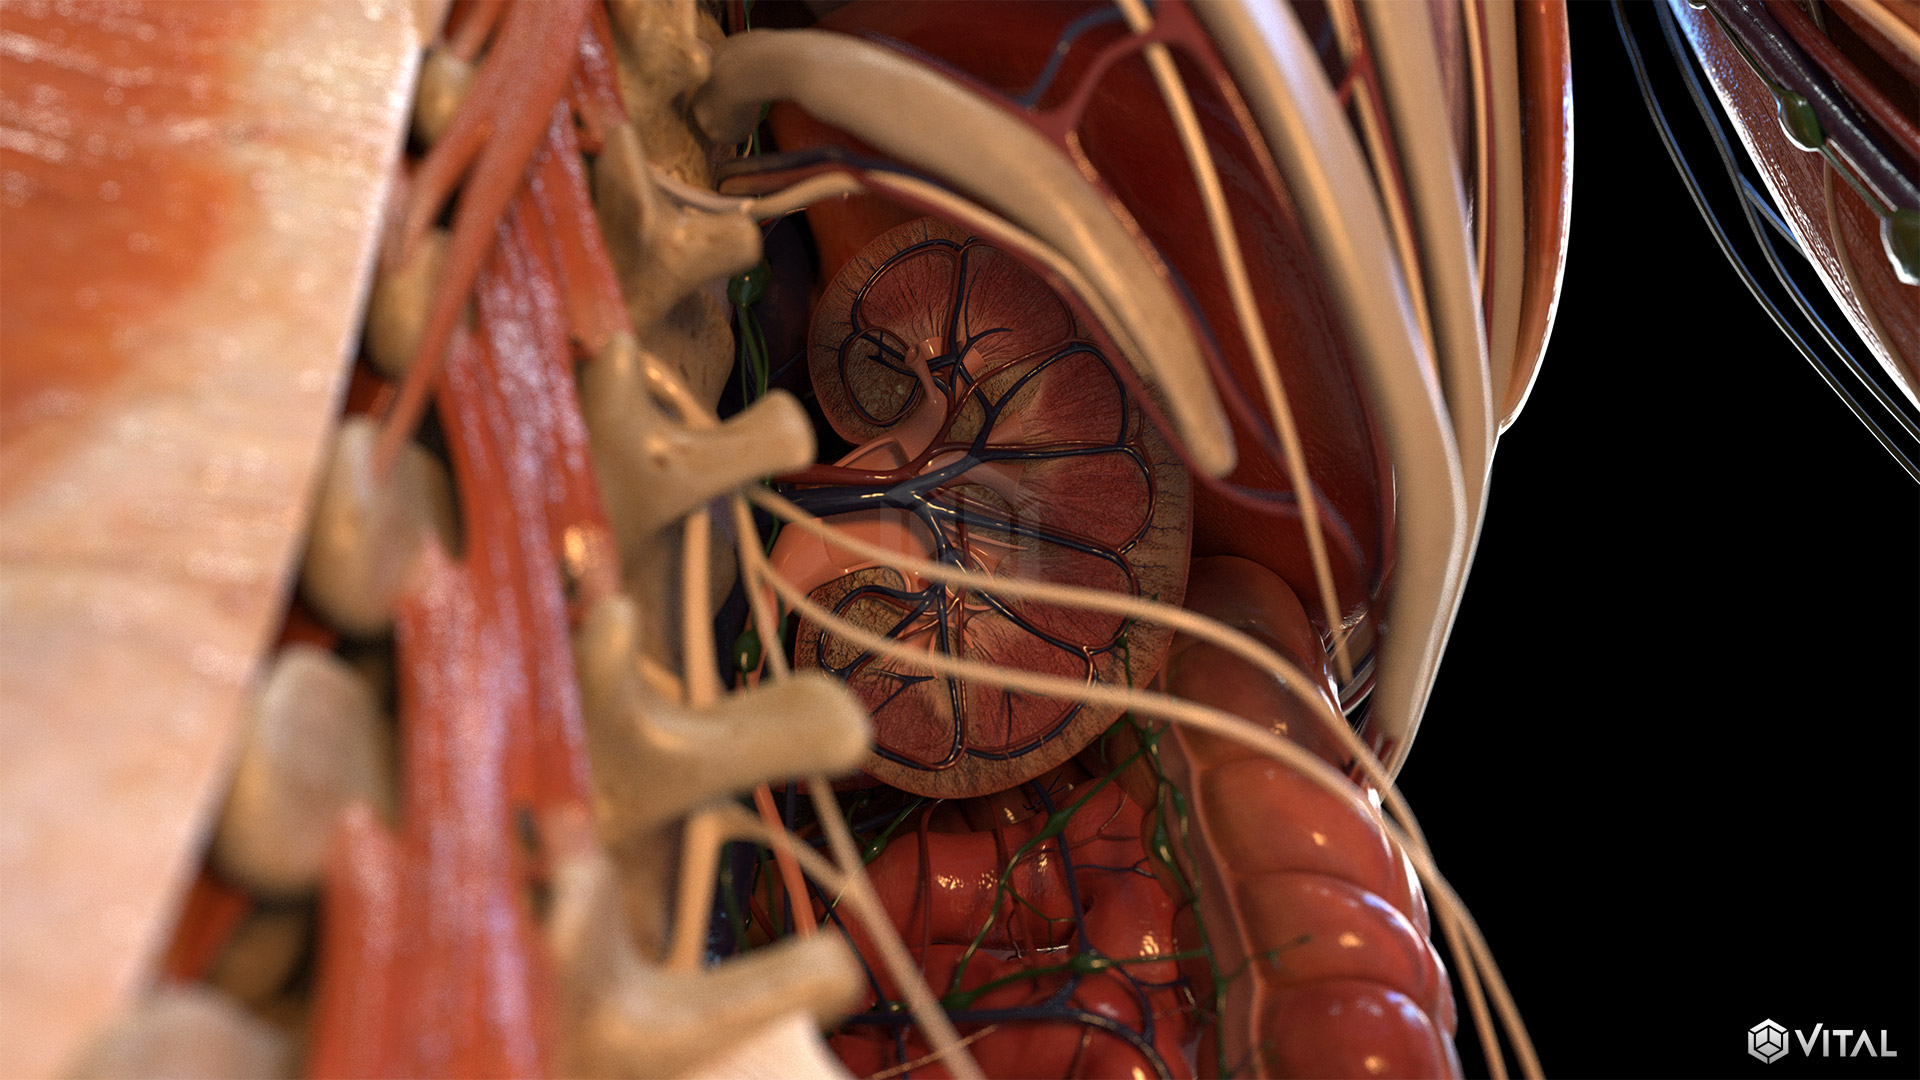

Medical

Vital and UET collaborate to support several clients throughout the medical industry. Together, we provide illustrations, animations, and trial exhibits to help depict complex anatomy and medical procedures clearly and precisely. We’re able to create an immersive, easy to understand learning experience, by combining real footage, such as captured ultrasounds, with correlating high fidelity 3D animation.